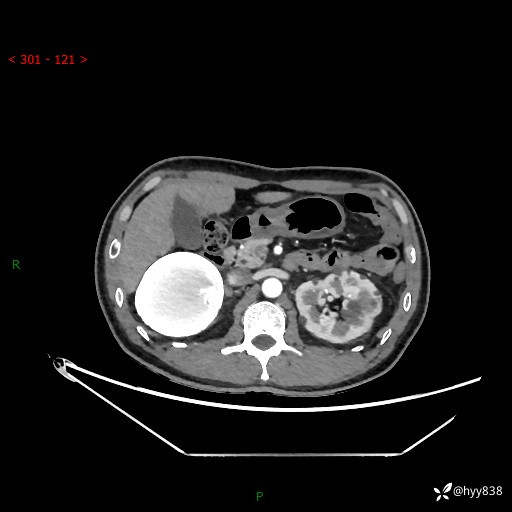

性别:男

年龄:50岁

简要病史:夜尿增多半月,发现肾功能异常1天,超声发现腹膜后占位

腹部CT平扫+增强

增强